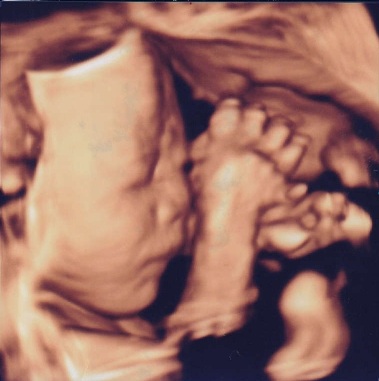

エコーはFujifilmの最新型の機械を導入しました。動く赤ちゃんを立体的にみられる4Dエコーも全例で実施します。赤ちゃんの位置や向きによっては上手くお顔が見えないことや、赤ちゃんによってはなぜかいつも背中しかみせてくれない子もいます。その点はご了承ください。

当院での4Dエコー画像例(患者様には掲載について了承をいただいております。)

27週 男の子